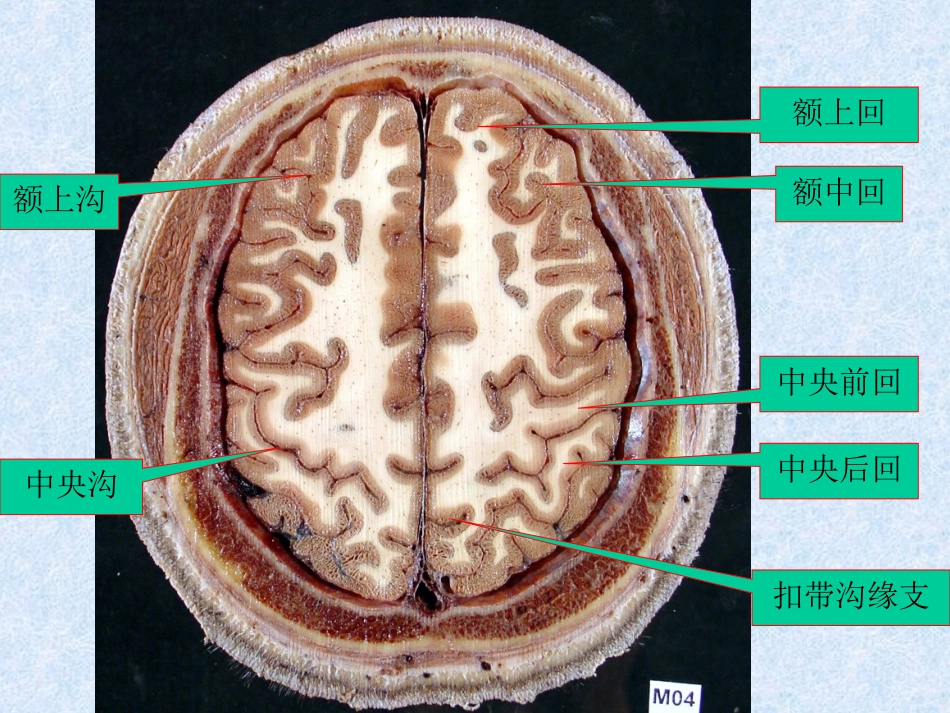

上矢状窦(四)脑叶、脑回横断层标本及CT、MRI1、横断层标本大脑镰头皮颅骨上矢状窦额上回中央前回中央沟额上回额中回中央前回中央后回额上沟中央沟扣带沟缘支中央前回中央沟楔前叶中央旁小叶顶内沟额窦顶上小叶侧脑室顶胼胝体干中央沟顶枕沟顶下小叶楔前叶额窦前钳侧脑室尾状核背侧丘脑顶枕沟角回缘上回外侧沟外侧沟水平部豆状核脑岛侧脑室后角第三脑室胼胝体压部前连合眶回直回内囊后肢尾状核头侧脑室三角部视放射距状沟筛窦眼球晶状体颞肌颞下回颞中回颞上回听辐射海马小脑幕小脑下矢状窦视束鼻中隔背侧丘脑侧脑室下角鼻泪管松果体垂体海绵窦中脑水管鼻中隔蝶窦小脑幕大脑脚环池眶下裂中鼻甲大脑镰咬肌上颌窦腮腺颞下颌关节窦汇乳突小房中耳小脑中脚第四脑室枕叶直窦横窦冠突第四脑室乙状窦上颌窦髁突下鼻甲齿...